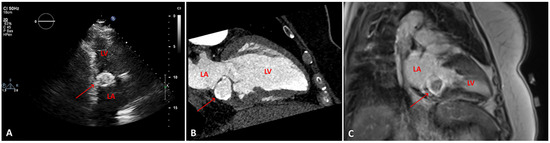

Myocardial infarction with nonobstructive coronary arteries (MINOCA): Myocardial infarction (MI) with non-obstructive coronary arteries (MINOCA) is defined as MI according to the fourth universal definition of MI [1] without coronary stenosis ≥50% on...